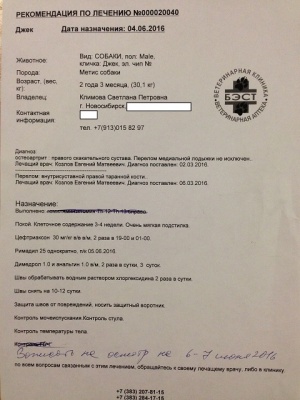

– предоплата за проведение компьютерной томографии правого скакательного сустава (КТ) врач Горшков Сергей Сергеевич, и операции (снятие пластины) хирург Козлов Евгений Матвеевич, клиника Бэст (чек 1, заключение КТ – документ 1, лист назначений – документ 1-1) – 5000 руб.;

– окончательная оплата за проведение компьютерной томографии правого скакательного сустава (КТ) врач Горшков Сергей Сергеевич, и операции (снятие пластины) хирург Козлов Евгений Матвеевич, клиника Бэст (чек 3, товарный чек 3, лист назначений – документ 3) – 7756 руб.;

– предоплата за проведение компьютерной томографии правого скакательного сустава (КТ) врач Горшков Сергей Сергеевич, и операции (снятие пластины) хирург Козлов Евгений Матвеевич, клиника Бэст (чек 1, заключение КТ – документ 1, лист назначений – документ 1-1) – 5000 руб.;

– окончательная оплата за проведение компьютерной томографии правого скакательного сустава (КТ) врач Горшков Сергей Сергеевич, и операции (снятие пластины) хирург Козлов Евгений Матвеевич, клиника Бэст (чек 3, товарный чек 3, лист назначений – документ 3) – 7756 руб.;

Лист приема и назначений от 15.06.2016, итоговый чек за период 02.03.2016 - 07.06.2016.